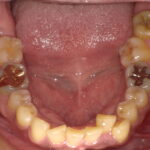

白い被せ物にしました!

こんにちは、大垣市の歯医者ビバ・スマイル歯科の歯科衛生士の山田です。 みなさん、 ...